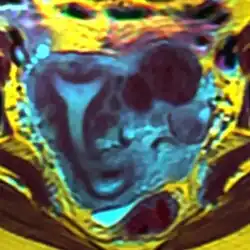

Arcuate uterus with fibroids seen on MRI